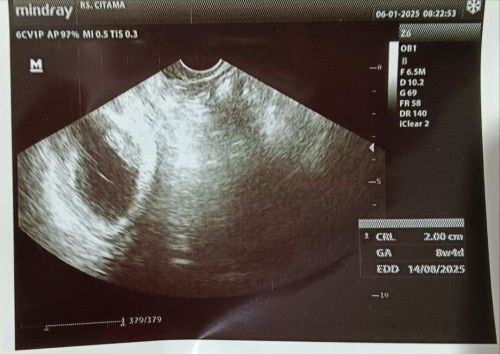

Alhamdulillah USG pertama anak ke 3 kalo hitungan hpht beda 2 hari tetep semangat. 💪🏻

Foto USG pertama! #sharing #Sharingdong_Bund